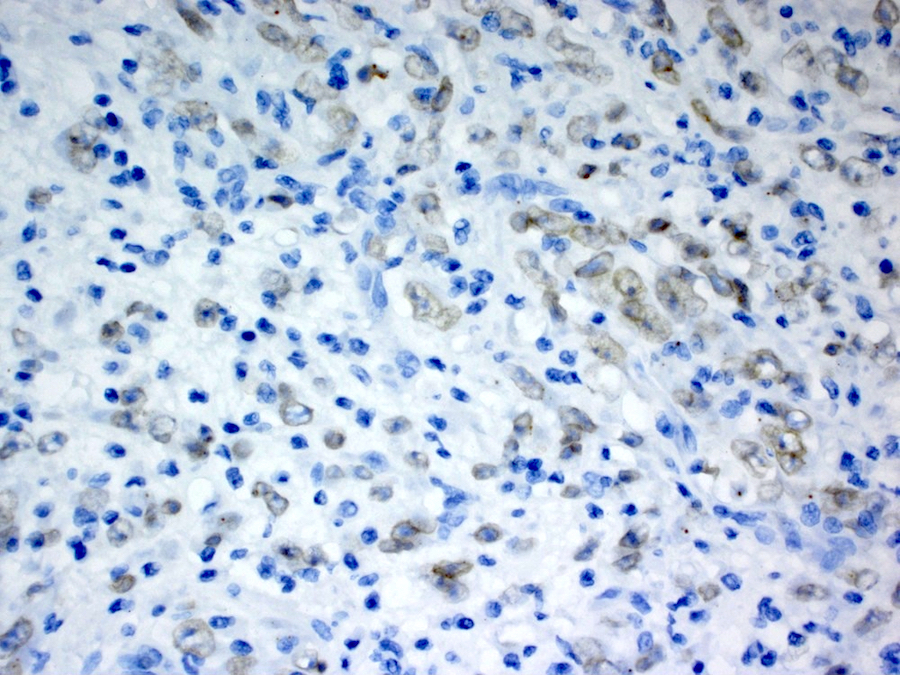

Contributed by Raul S. Gonzalez, M.D.

Contributed by Michael Feely, D.O.

Positive stains

- Desmin, smooth muscle actin; variable cytoplasmic ALK1 (Mod Pathol 2002;15:931)

- Epithelioid inflammatory myofibroblastic sarcoma: nuclear membrane ALK1

A young male patient presents with abdominal pain. Imaging reveals a large mesenteric mass, which is resected. An image of the tumor’s histology is seen above. Immunohistochemistry shows ALK1 staining of the nuclear membranes. What molecular abnormality is present in this tumor?